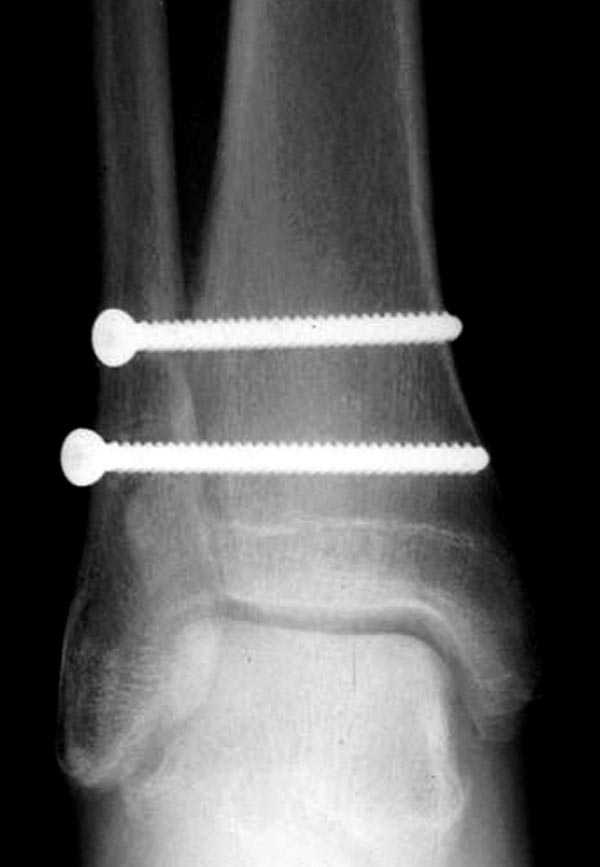

здесь пропускаем повреждение Maisonneuve...

Здесь как раз тот случай, когда рентгеновский снимок скрывает главную проблему. "Ходит, прихрамывая на правую ногу, отмечает боли в правом голеностопном суставе" По описанию клиника типичная для повреждения голонестопного сустава - синдесмоза.

При проксимальных переломах малоберцовой автоматически необходимо подозревать повреждение синдесмоза - Maisonneuve Fracture.

Описанное в 1840 году Maisonneuve повреждение характеризуется тем, что при фиксированной наружной ротации стопы повреждается передняя фибуло-тибиальная связка, часть синдесмоза, с переломом медиальной лодыжки и без, дальше разрыв продолжается по межкостной мембране и спиральный или косой перелом малоберцовой происходит выше.

Невозможно устранить проблему фиксацией малоберцовой пластиной или другими методами, потому что главная проблема - разрыв межберцовой мембраны, которая находится между костями и внизу в голеностопе в синдесмозе.

Две параллельных шурупа создают условия для сращения мембраны и синдесмоза, 8 недельный срок достаточен, и можно удалить фиксаторы.